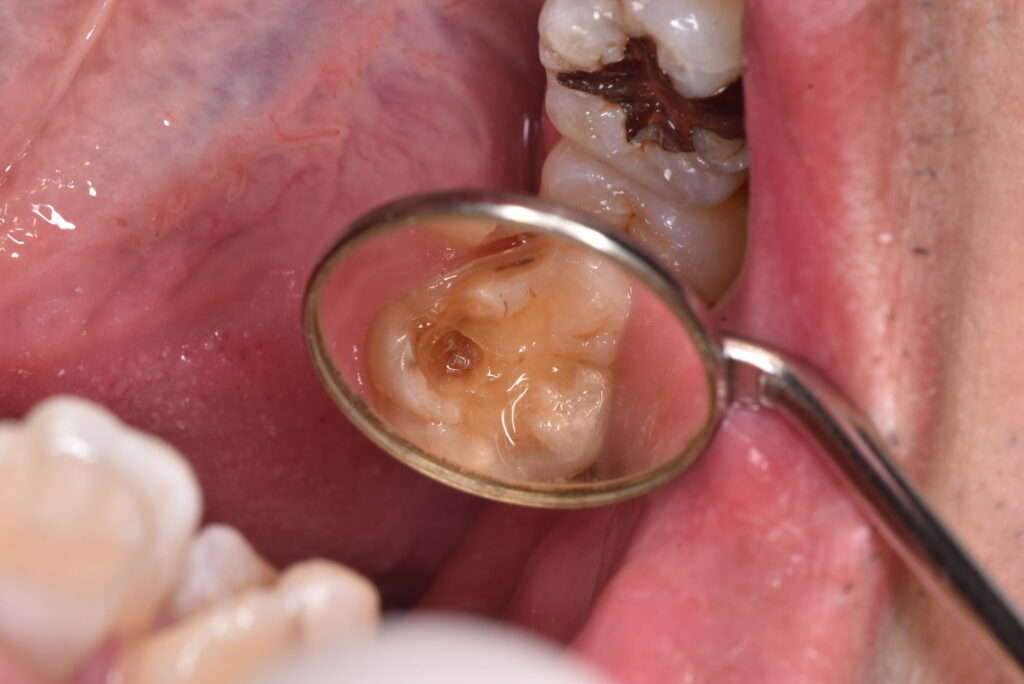

取り切った写真が下になります。神経にかなり近い部分まで虫歯が広がっていました。神経が出なかったのは幸いですが、症状が出ても全くおかしくないケースです